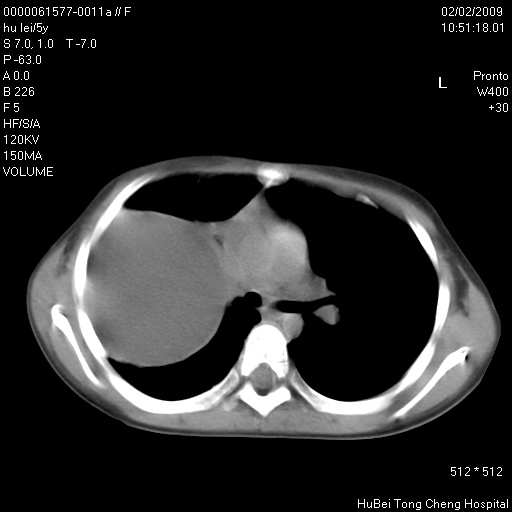

标题: PED1732:M5Y,右肺囊性占位!

患者:男,5。无明显不适,拍胸片考虑右肺囊肿。

行ct扫描,图象如下:

病灶与前胸壁和右上纵隔、叶间裂界限不清,病灶前缘及内侧缘看不到正常的肺组织,不能排除包裹性积液。